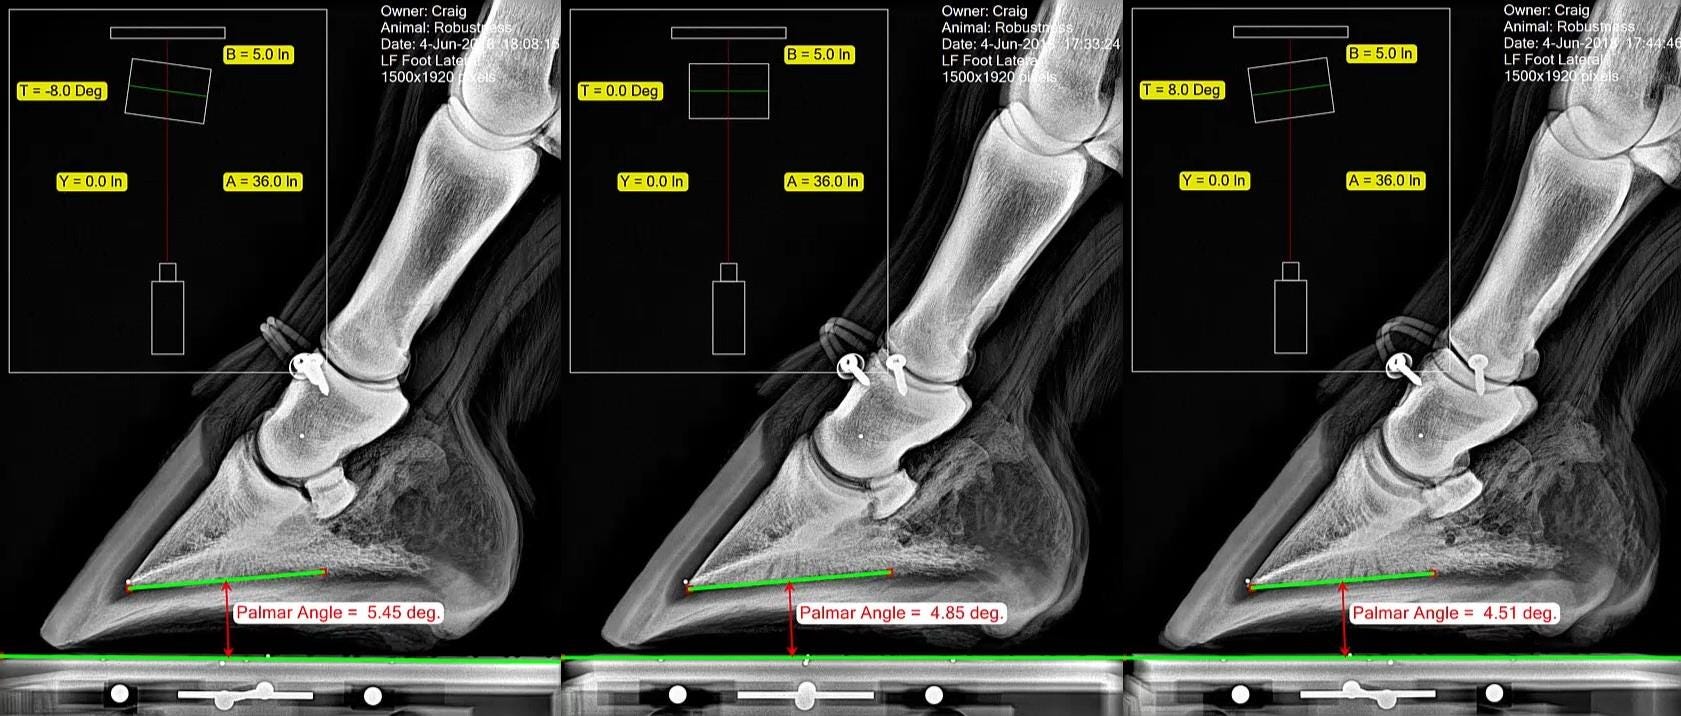

Measuring the Equine Hoof in Radiographs — a Focus on Calibration by

From medium.com

Measuring the Equine Hoof in Radiographs — a Focus on Calibration by How To Measure Hoof Angles The angle of the long pastern bone; The sound the hoof makes; Learning how to measure hooves, and what those measurements mean to the health of your horse, is an important part of natural hoof care. You may have seen your farrier use it. If this angle, or line, is broken, it indicates a poor trim due to either too. How To Measure Hoof Angles.

Measuring the Equine Hoof in Radiographs — a Focus on Calibration How To Measure Hoof Angles This angle is often measured mechanically with the help of hoof gauge. The angle of the long pastern bone; Hoof angle dos and don’ts. Hoof expert susan kauffmann describes three hoof angles you should know to help keep your horse sound. Learn how to identify and assess them. Popular methods to determine the proper hoof angle have relied on: A. How To Measure Hoof Angles.

Measuring the Equine Hoof in Radiographs — a Focus on Calibration by How To Measure Hoof Angles Learn how to identify and assess them. You may have seen your farrier use it. If the horse is working really well, and is comfortable and sound, it might be a good idea to measure the hoof to record the exact angles, lengths, and other measures that make that. The angle of the long pastern bone; Regardless as to whether. How To Measure Hoof Angles.